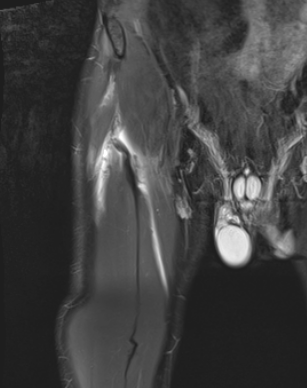

Chronic Grade 4 proximal rectus tear

Grade 4B Rectus femoris musculotendinous injuries